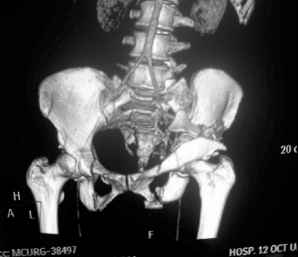

41 yo female , fall from 10 meters five days ago. Hemodynamically unstable on admission treated by angio and embolization and skeletal traction, with no external support. No associated injuries.

Based on CT scan the pt has a both column fracture with conminuted dome and displaced anterior column and a sacral Denis 1 fracture with a displaced left ala. I think the best approach for the acetabular fracture is ilioinguinal with Smith-Petersen extension but don't know exactly the sequence . Will you start with the sacral fracture? Which technique?